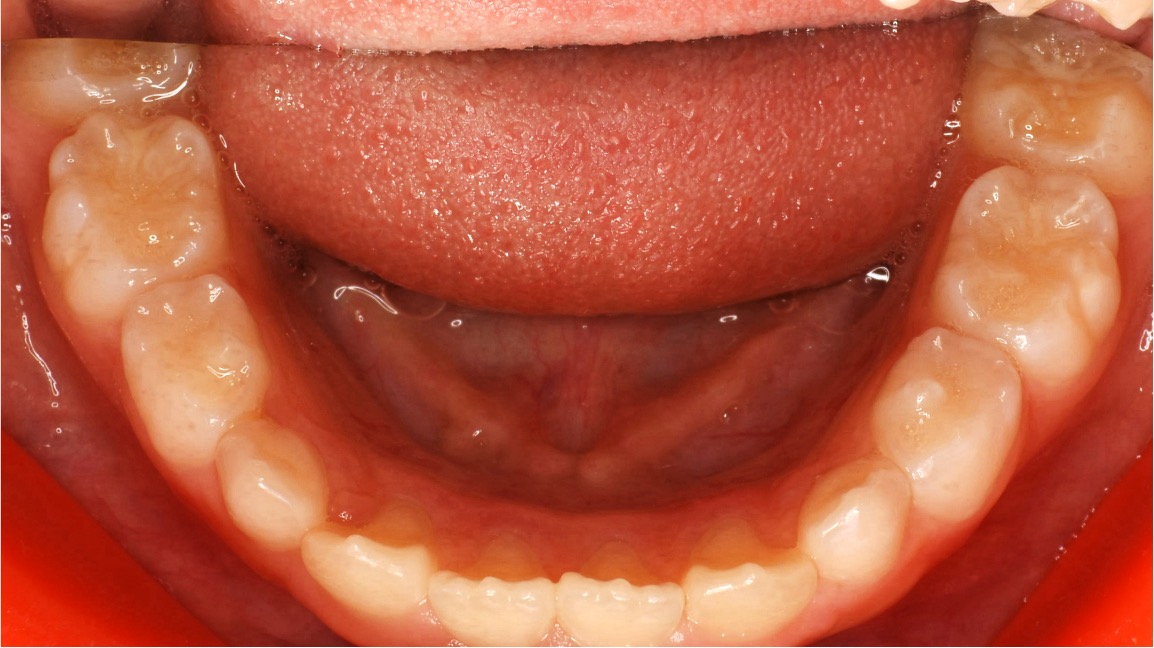

治療前の歯並び

6歳の時、顎が小さく、永久歯が内側に重なって生えている。